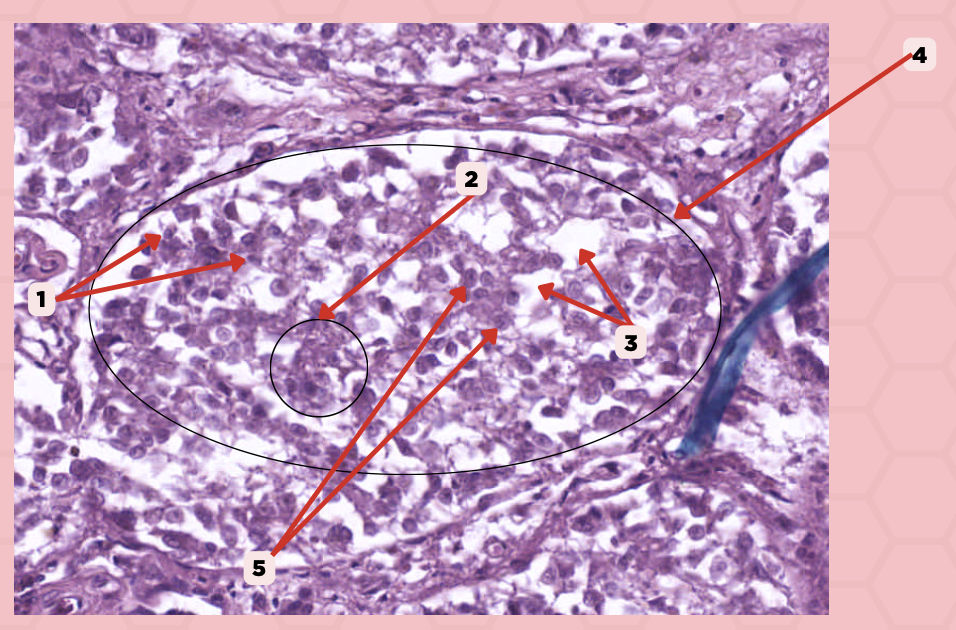

Identify the specimen.

Lobule

Identify the structure labeled as 1.

#5 Pinealocytes (Chief Cells)

Which among these structures are modified neurons that are responsible for synthesizing melatonin?

#1 Interstitial Cells

Which among these are supporting cells that are morphologically similar to astrocytes?

Interstitial Cells

Identify the structure labeled as 1.

Clusters (Cords) of Cells

Identify the structure labeled as 2.

Capillaries

Identify the structure labeled as 3.

Lobule

Identify the structure labeled as 4.

Pinealocyte

Identify the structure labeled as 5.